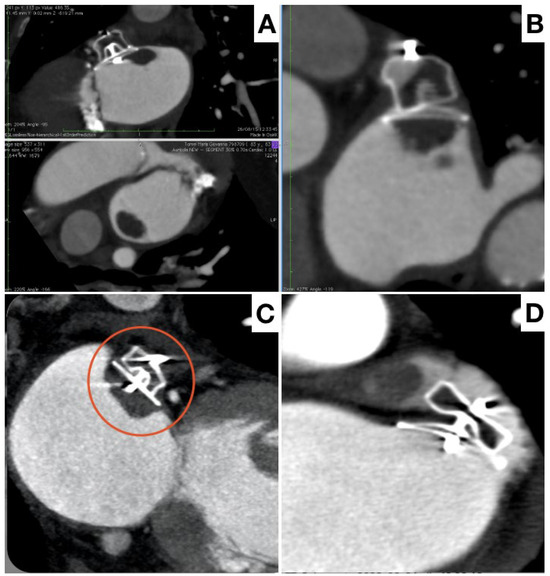

- Korsholm, K.; Jensen, J.M.; Nørgaard, B.L.; Nielsen-Kudsk, J.E. Detection of Device-Related Thrombosis Following Left Atrial Appendage Occlusion: A Comparison Between Cardiac Computed Tomography and Transesophageal Echocardiography. Circ. Cardiovasc. Interv. 2019, 12, e008112. [Google Scholar] [CrossRef] [PubMed]

- Clemente, A.; Avogliero, F.; Berti, S.; Paradossi, U.; Jamagidze, G.; Rezzaghi, M.; Della Latta, D.; Chiappino, D. Multimodality imaging in preoperative assessment of left atrial appendage transcatheter occlusion with the Amplatzer Cardiac Plug. Eur. Heart J. Cardiovasc. Imaging 2015, 16, 1276–1287. [Google Scholar] [CrossRef]

- Korsholm, K.; Jensen, J.M.; Nørgaard, B.L.; Samaras, A.; Saw, J.; Berti, S.; Tzikas, A.; Nielsen-Kudsk, J.E. Peridevice Leak Following Amplatzer Left Atrial Appendage Occlusion: Cardiac Computed Tomography Classification and Clinical Outcomes. JACC Cardiovasc. Interv. 2021, 14, 83–93. [Google Scholar] [CrossRef]